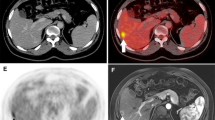

WB-MRI detected 27 hepatic metastases in 15 patients (mean size 22 mm ± 4 mm; range 3–42 mm); the smallest hepatic metastasis was 3 mm in diameter (n = 2). PET-CT revealed 23 hepatic metastases in 15 patients identifying a lesion as small as 4 mm (mean size 13 mm ± 4 mm; range 4–38 mm) (Fig. 3). There was always a good correlation between morphologic imaging of WB-MRI and functional imaging of PET-CT regarding evaluation of intralesional necrosis and peripheral activity (Fig. 4). One 8 mm hepatic metastasis, with significance uptake and contrast-enhancement on PET-CT, was not visible on WB-MRI (Fig. 5).

Sixty-four years-old patient with colorectal carcinoma who underwent thermoablation for hepatic metastasis at the time of surgery, 2 years follow-up. Coronal (A) and axial (B) PET-CT fused images, coronal T2W TSE STIR WB-MRI (C), T1W 3D FFE post-contrast axial images (D, E). A large hepatic metastasis is well visible on left liver on both PET-CT and WB-MRI. PET-CT shows no activity in the site of previous thermoablation (arrow) with no contrast enhancement on T1W 3D FFE post-contrast images (arrowheads).

Sixty-eight years-old patient with right liver metastasis. Coronal T2W TSE WB-MRI (A), coronal and axial PET-CT fused images (B, C) and T1W 3D FFE post-contrast coronal reformation image (D) at the same level; T1W 3D FFE pre-contrast (E) and post-contrast (F) axial images. On PET-CT axial image (C) is well defined the peripheral uptake of the lesion properly correlated with the rim-enhancement displayed on T1W FFE post-contrast image (arrowhead), demonstrating the necrotic area and the surrounded active portion of the lesion.

Sixty-three years-old patient with hepatic metastases 3 years after surgery. Coronal (A) and axial (B, C) PET-CT fused images, post-contrast axial CT image (E), T1W FFE post-contrast WB-MRI coronal (D) and axial T1W 3D FFE post-contrast image (F). Two hepatic metastases are well visible (arrows) on PET-CT images (A–C). There is a tight correlation PET-CT/WB-MRI on coronal images for the larger hepatic lesion while the smaller 6 mm lesion is well evident on post-contrast CT image (E, arrowhead) and fused PET-CT image (C) but is not visible on axial T1W 3D FFE post-contrast image, probably due to respiratory motion artifacts.